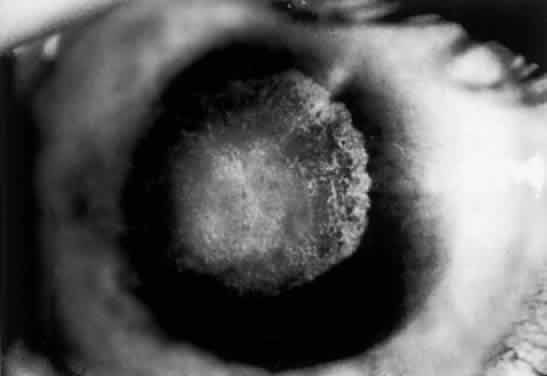

Nonsystemic Familial Type. Lattice corneal dystrophy (Biber-Haab-Dimmer) is usually considered to be a localized amyloidosis of the cornea and could be classified as a special type of primary localized autosomal dominant amyloidosis (see corneal dystrophies section) (Fig. 6).78 Rarely, a form of primary familial amyloidosis of the cornea may occur. The lesions appear as centrally located, raised, gelatinous masses with a mulberry-like surface (Fig. 7).79

Fig. 6. Lattice dystrophy. Localized amyloid of the cornea. Corneal changes are shown in retroillumination.

Fig. 7. Rare primary familial amyloidosis.